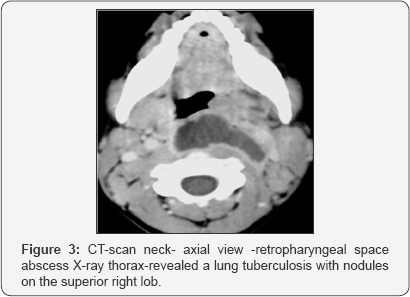

Cervical spine tuberculosis is a less common presentation but is potentially more serious because severe neurologic complications are more likely. This condition is characterized by pain and stiffness. Patients with lower cervical spine disease can present with dysphagia or stridor. Symptoms can also include torticollis, hoarseness, and neurologic deficits (Figures 3-5).

Percutaneous, CT scan guided needle biopsy of bone lesions for anatomo-pathologic studies is very important Biopsy from granulation resulted from surgical drainage of abscesses Microbiologic studies to confirm diagnosis and to isolate organisms for culture and susceptibility. Frequent negative Drainage Some cases of Pott disease are diagnosed following an open drainage procedure (eg, following presentation with acute neurologic deterioration) Figures 6 & 7.

CT Scanning neck, thorax

• CT scanning provides much better bony detail of irregular lytic lesions, sclerosis, disk collapse, and disruption of bone circumference. Low-contrast resolution provides a better assessment of soft tissue, particularly in epidural and paraspinal areas.

• CT scanning reveals early lesions and is more effective for defining the shape and calcification of soft-tissue abscesses. In contrast to pyogenic disease, calcification is common in tuberculous lesions.